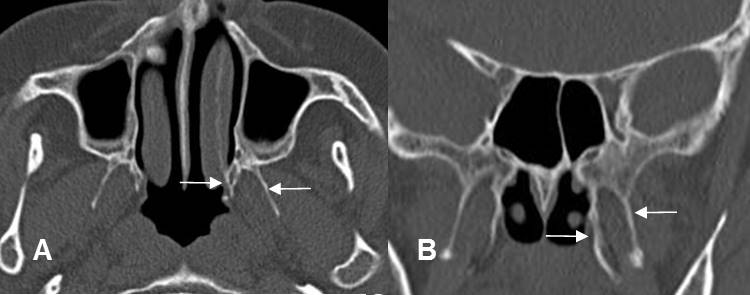

Fig 219. Láminas pterigoideas.

A: TAC axial y B: TAC reconstrucción coronal. Láminas pterigoideas  normales.

Fig  220. Fractura de láminas pterigoideas.

A: TAC axial y B: TAC reconstrucción coronal. Fracturas de las láminas pterigoideas, hallazgo indispensable para hace el diagnóstico de fractura de Le Fort.